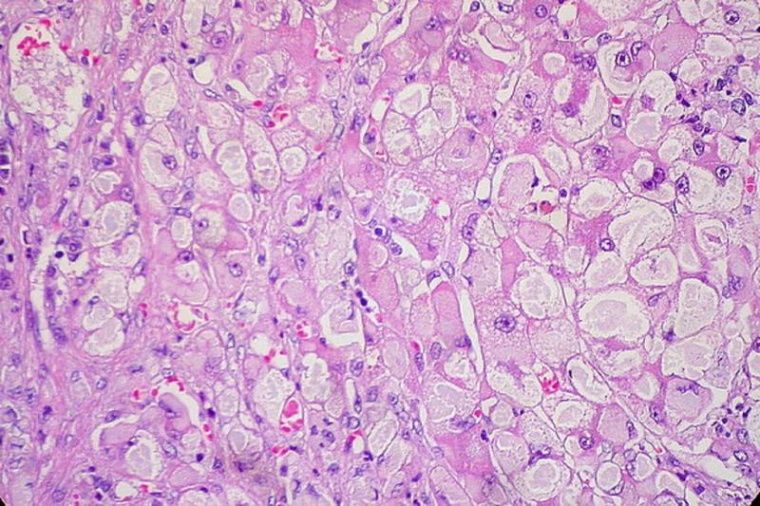

Die Wissenschaftler entnahmen kleine Stücke der Leber (Biopsien) von Patienten, die sich in der MASH-Klinik am Addenbrooke's Hospital in Cambridge UK einer Diagnose unterzogen. Anschließend führten sie Einzelzellanalysen durch, um die zugrunde liegenden Mechanismen zu ermitteln. Die Biopsien stammten von Patienten in verschiedenen Krankheitsstadien, sodass sich erstmals das Fortschreiten der MASLD beim Menschen darstellen ließ. Sie entdeckten einen interessanten Mechanismus: Chronische Leberschäden veränderten die Leberarchitektur stark, insbesondere die Struktur der drei Gallengänge - ein Netz von Leitungen, die die Leber von Giftstoffen entwässern. Diese Umstrukturierung ist mit einem Regenerationsprozess verbunden, der als Transdifferenzierung bezeichnet wird.

"Wir wussten, dass das Fortschreiten der Krankheit eine Proliferation der Cholangiozyten, der Hauptzellart der drei Gallengänge, auslösen kann. Wir haben jedoch nicht erwartet, dass diese Proliferation organisiert abläuft und zur Bildung eines so komplexen Netzwerks führt, das die Architektur der Leber stark beeinträchtigt", berichtet Vallier.

Das Fortschreiten der Krankheit geht mit Zeichen der Regeneration einher

"Nun wollten wir natürlich wissen, ob dieser Prozess ein Zeichen dafür ist, dass die Leber versucht, sich selbst zu reparieren oder dass die Schädigung fortschreitet. Dazu haben wir detaillierte Einzelanalysen durchgeführt und festgestellt, dass Cholangiozyten offenbar in Hepatozyten, den wichtigsten funktionellen Zelltyp der Leber, transdifferenzieren. Das Organ versucht also verzweifelt, die funktionellen Zellen zu ersetzen, die während der Krankheit absterben", erklärt Vallier.

Die meisten Transdifferenzierungsvorgänge finden in der letzten Phase der Krankheit statt, wenn die Leber stark geschädigt ist. Dieser Regenerationsprozess ist also mit dem Fortschreiten der Krankheit verbunden und scheint nicht direkt durch eine Verletzung ausgelöst zu werden. Darüber hinaus sind Lebererkrankungen im Endstadium stark mit Leberkrebs verbunden, während eine Reihe von Faktoren, die die Transdifferenzierung in vivo und in vitro zu fördern scheinen, auch in Lebertumoren stark ausgeprägt ist. Demnach könne Krebs aus einem schief gelaufenen Regenerationsprozess entstehen. In der Tat könnten chronische Verletzungen und eine kranke Mikroumgebung eine große Menge an Stress auf die Zellen ausüben, die dann "plastisch" werden und somit in der Lage sind, zu transdifferenzieren. Dieser Erwerb von Plastizität könnte jedoch abnormal werden, wenn er zu weit geht.